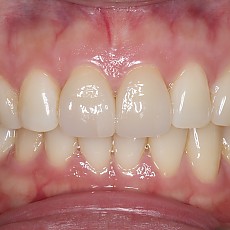

시술전후사진 6 페이지

Total 189건 6 페이지